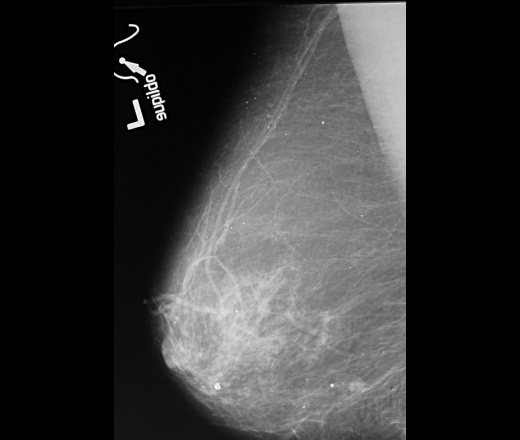

как хорошо виден на прицеле злокачественное узловое образование с микрокальцинатами